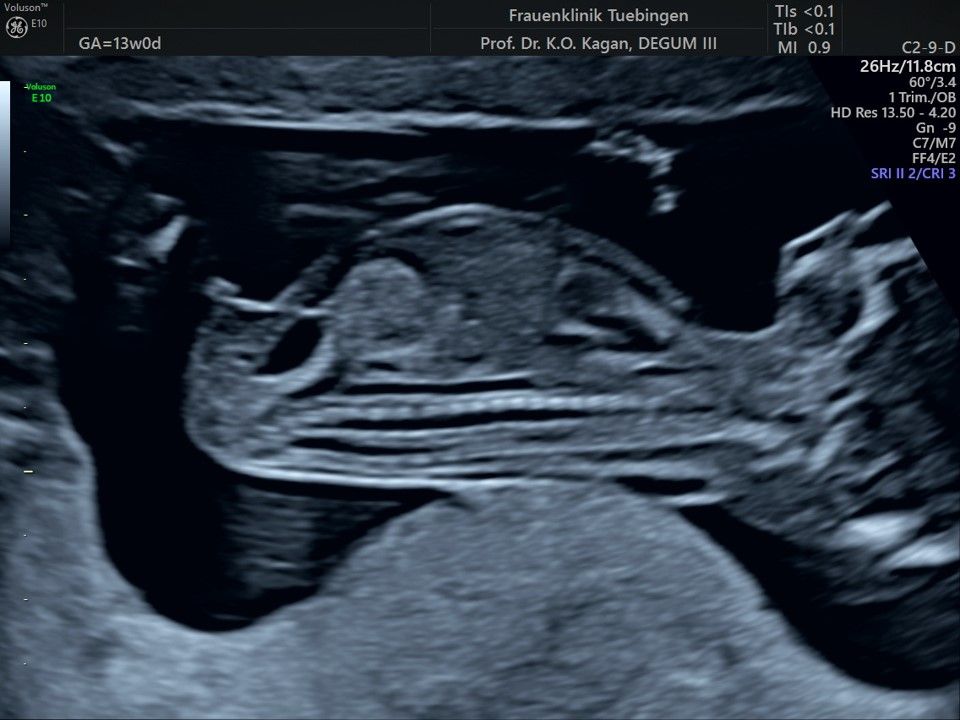

Im Rahmen des Ersttrimester-Screenings untersuchen wir die Organe des Feten mittels Ultraschall. Dabei machen wir auch gerne ein Bild für Sie.

Obwohl der Fet zu diesem Zeitpunkt erst zwischen 5 und 8cm groß ist, lassen sich bereits etwa die Hälfte aller schwerwiegenden Fehlbildungen erkennen bzw. ausschließen. Sollten wir eine Auffälligkeit sehen, werden wir mit Ihnen den Befund und das weitere Vorgehen ausführlich besprechen.

Das Ergebnis der Ultraschalluntersuchung ist wegweisend. Dabei wird der Fet vermessen, die Organe werden untersucht und die sonographischen Marker zur Risikoberechnung für Chromosomenstörungen werden beurteilt. Das sind: die Nackentransparenzdicke, Nasenbein sowie der Blutfluss in der rechten Herzhälfte und im Ductus venosus, einem Gefäß in der Leber des Feten.